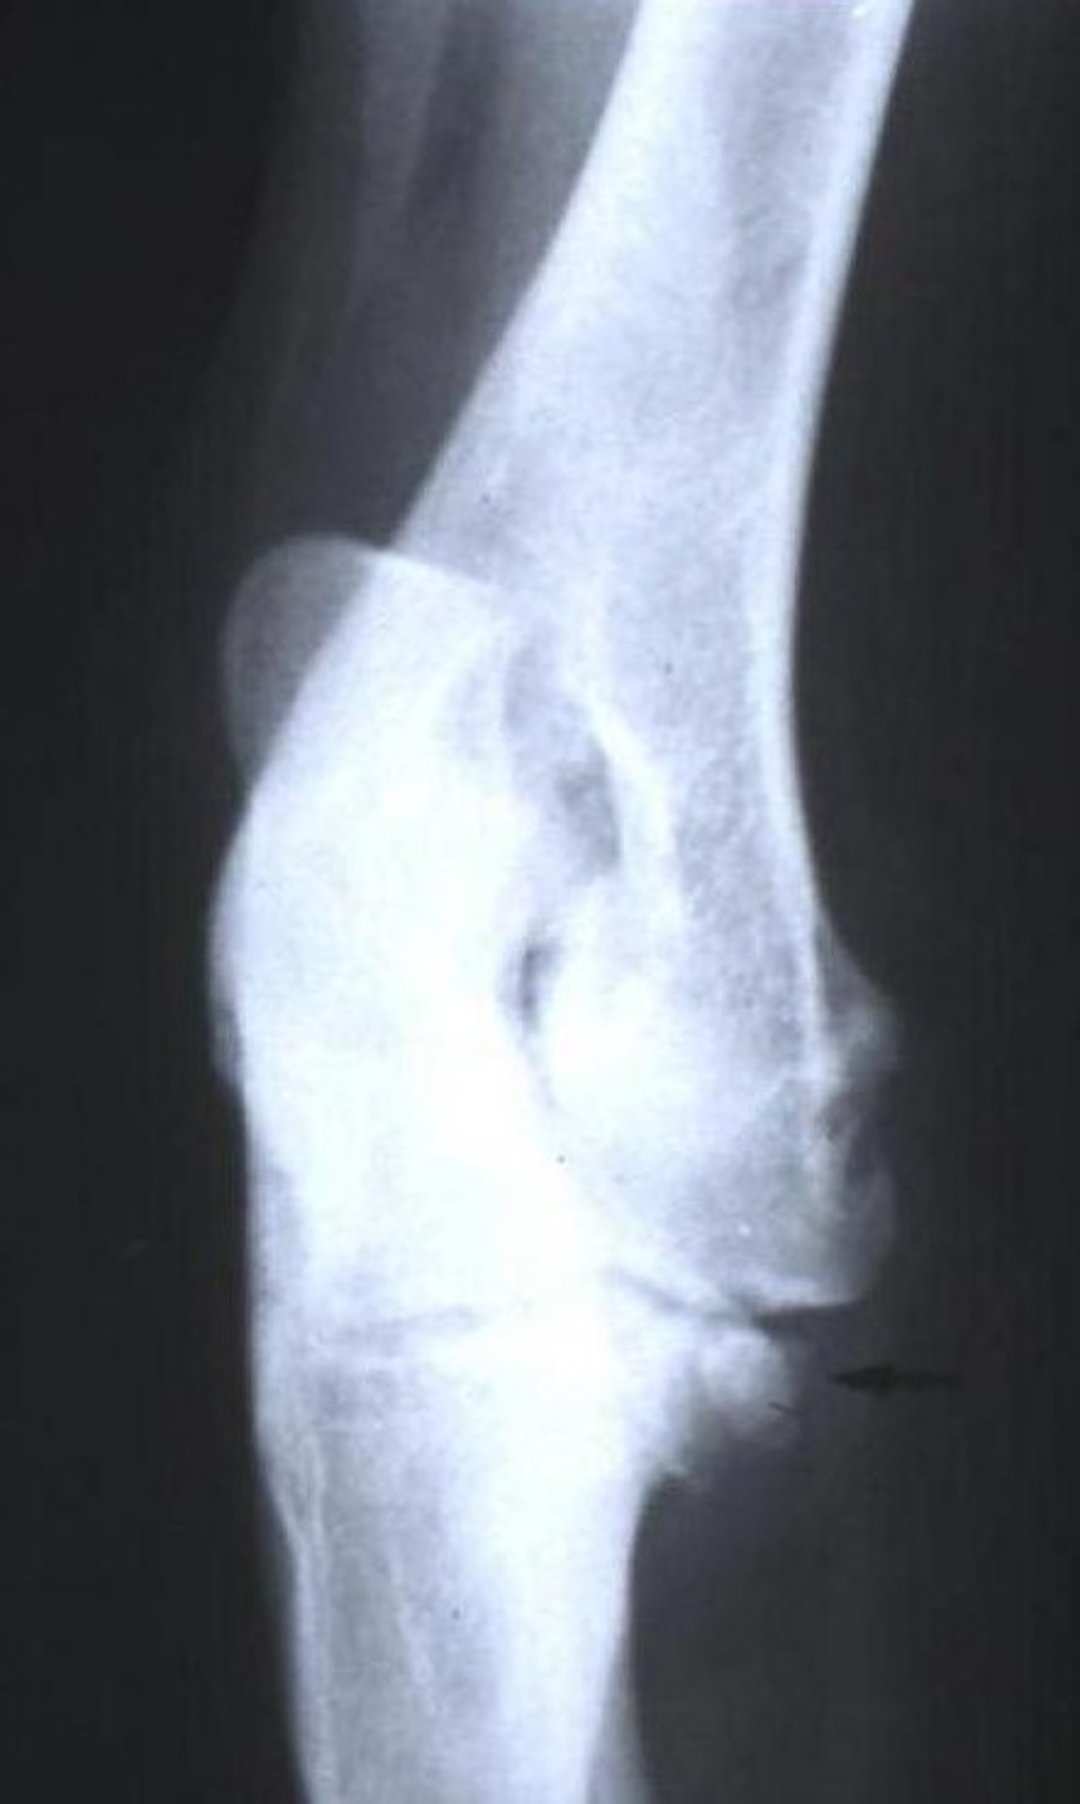

Craniocaudal oblique radiographic view of the right elbow of a dog with medial coronoid disease. Note the exostosis in the proximal medial region of the ulna.